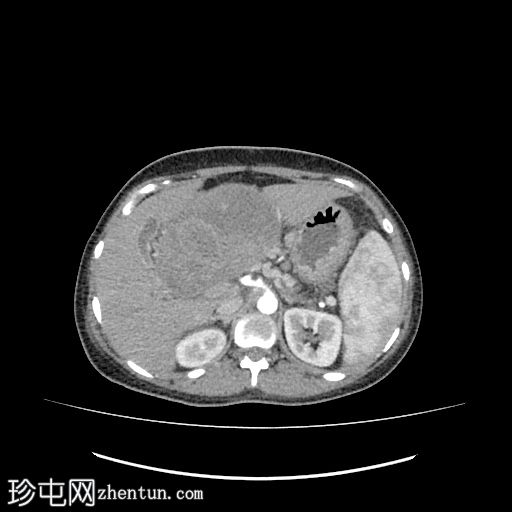

轴位增强扫描

动脉期

2.jpg

肝下区可见一大小约15 x 15.2 x 8.6 cm的较大、边界清晰、呈不均匀强化的实性肿块。

该病灶压迫胃小弯、幽门和胃窦,并对肝脏产生占位效应。门静脉和下腔静脉受压,但脂肪间隙保持完整,未见明确的血管侵犯。

肿块左侧可见正常的胰尾。胰管未见扩张。

病例讨论

影像学检查显示肝下/上腹部存在一个边界清晰、以实性为主的异质性肿块,对邻近结构造成压迫,但脂肪间隙保持完整,且未见明确的血管侵犯,这些特征符合实性假乳头状上皮肿瘤(SPEN)的诊断。

胆道系统和上游胰管未见扩张,这是该生长缓慢的肿瘤的显著特征。

行手术切除,活检证实为SPEN。